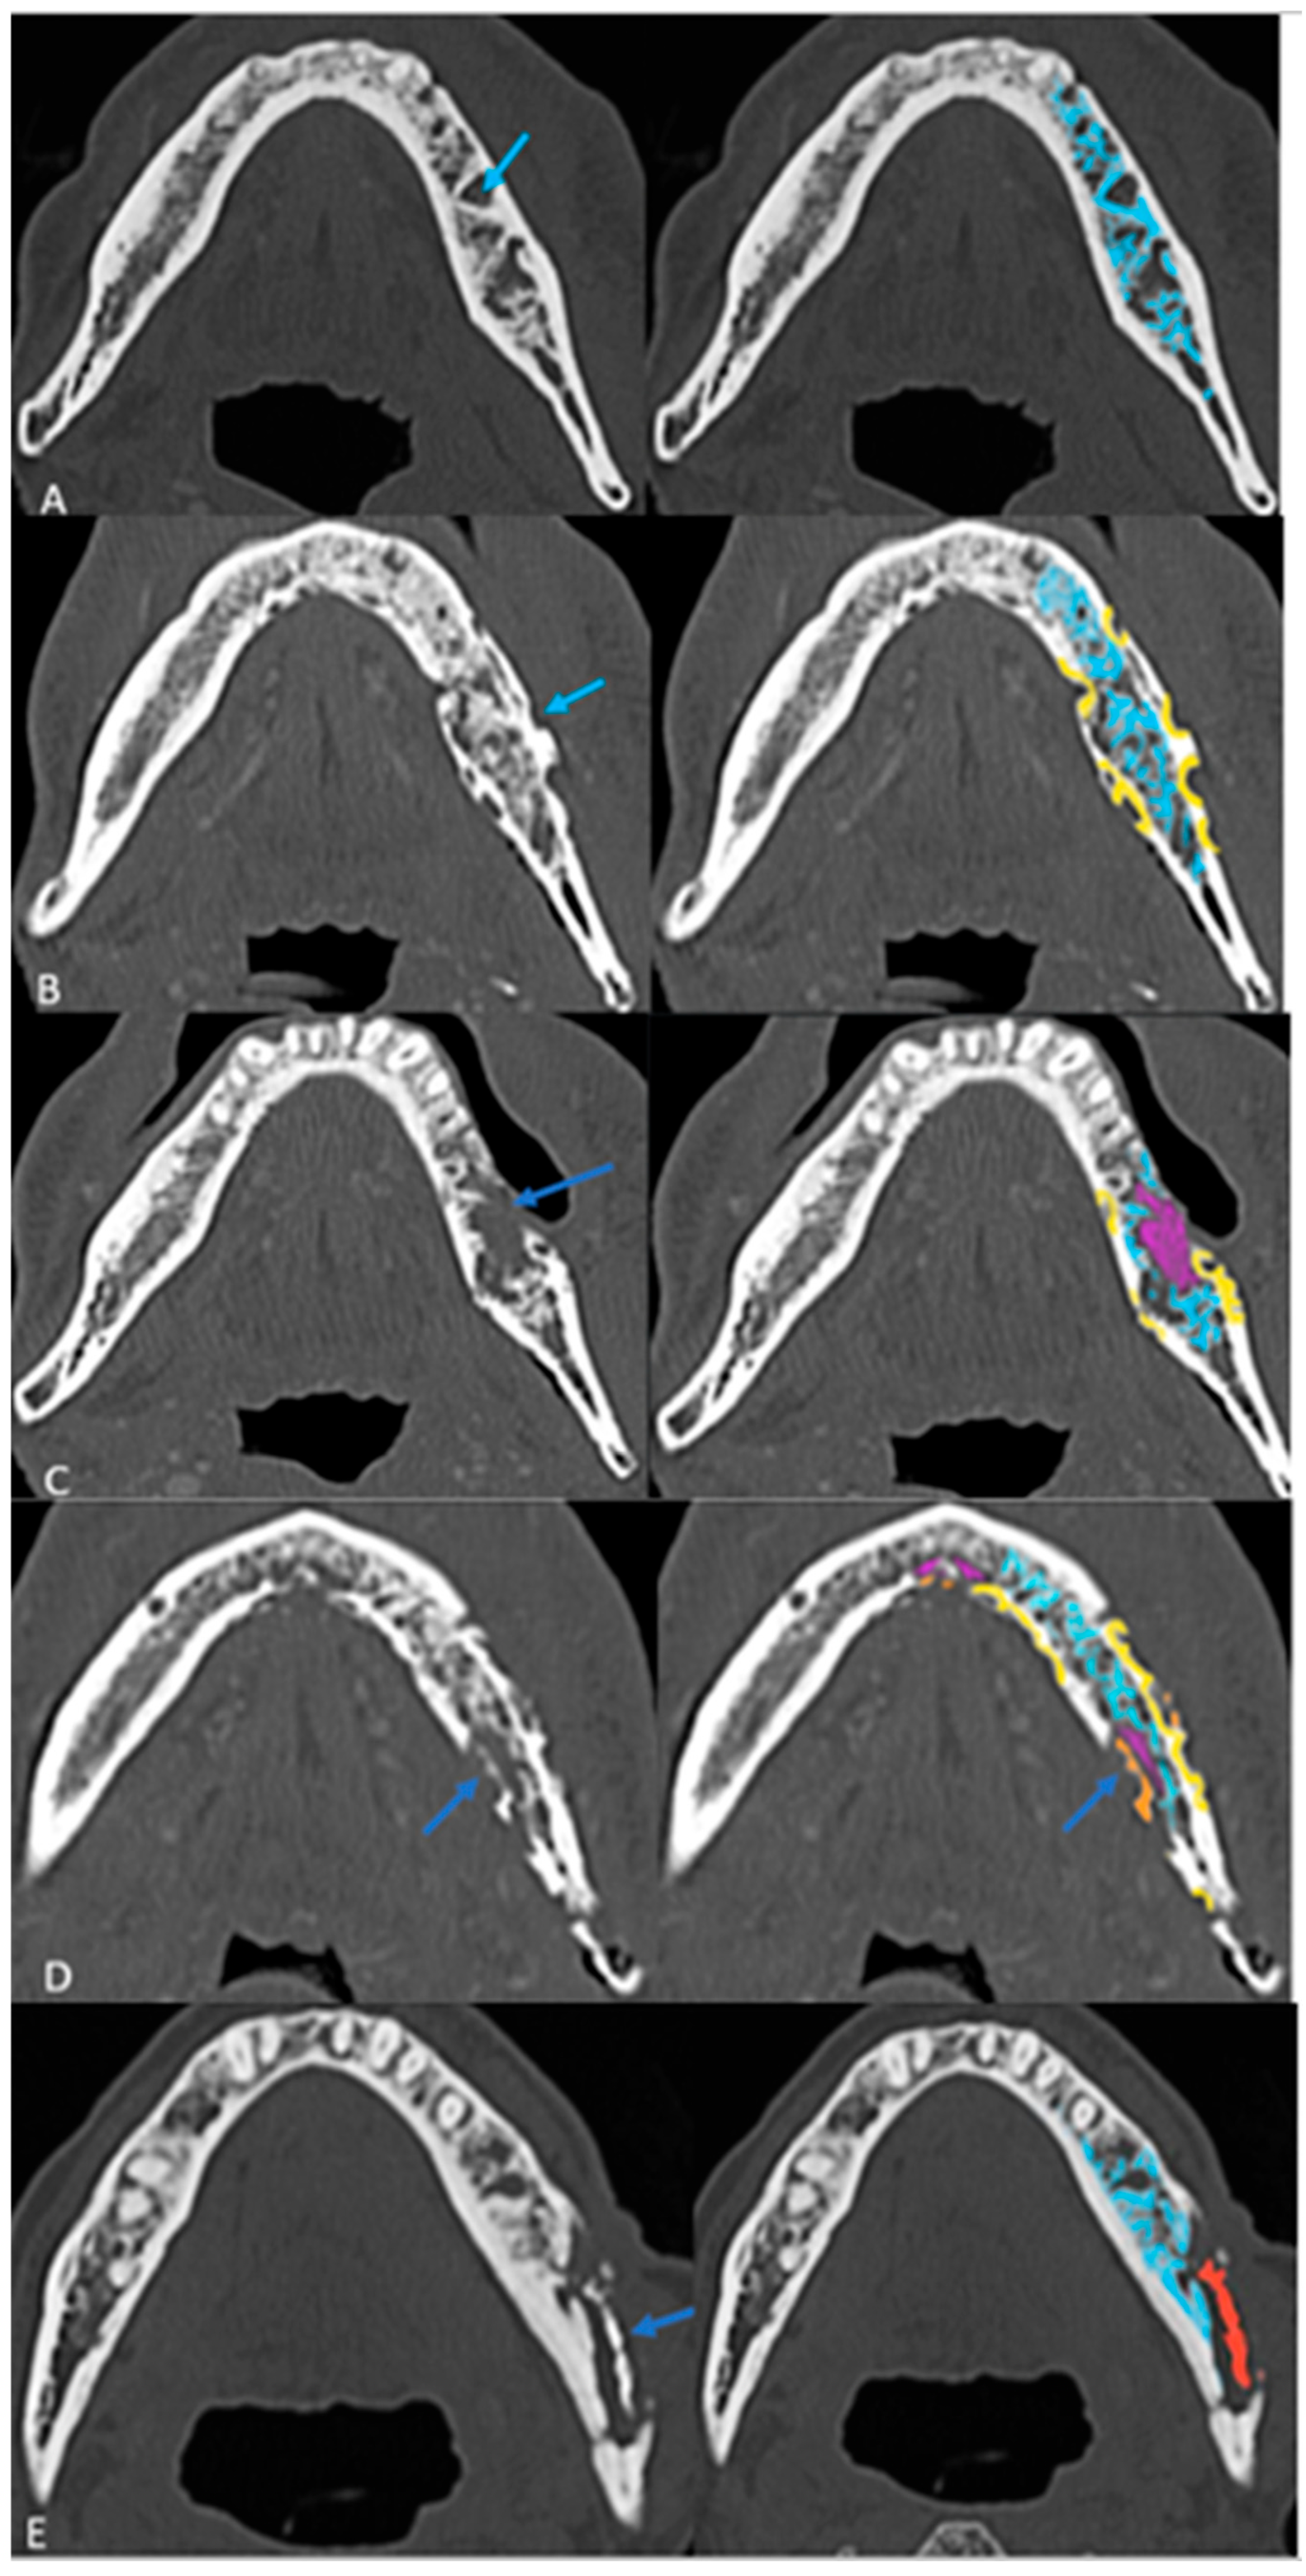

3.3. Radiological Progression and Proposed Grading System

Follow-up imaging demonstrated the progression of ORN in most cases, with increased bone resorption (77%), fragmentation (92%), and sclerosis (92%). Sequestrum formation and intraosseous gas appeared in later stages, while periosteal reaction was rare (3%), differentiating ORN from osteomyelitis. Neither intraosseous gas nor orocutaneous fistulae are an indicator of severity per se. Soft tissue involvement was less than bone destruction, and its isoenhancing nature on CT helped to distinguish ORN from tumor recurrence. This analysis of radiological evolution of ORN leads us to propose a four-step grading system that builds on ClinRAD to aid in diagnosis (Figure 4A–E).

Figure 4. The proposed structured grading system of ORN on axial CT images: (A) Grade 0: Resorption (Early Stage) with thickened and sparse trabecular (blue). (B) Grade 1: Partial thickness cortical resorptions (yellow). (C) Grade 2: Full-thickness cortical resorption with medullary extension (pink areas). (D) Grade 3: Fragmentation/fracture (Orange). (E) Grade 4: Sequestrum (red) (End Stage).

Based on these findings, a structured grading system was proposed (Figure 4A–E) (Table 3).

• The presence of sclerosis in varying proportions in most cases does not fit into a specific evolutionary stage and was therefore excluded from grading.

• The proposed grading system contributes to understanding the extent of ORN on imaging and clarifying early vs. late diagnosis. Larger studies are warranted to validate this grading system and refine its criteria.

In contrast, our imaging-based grading system (Grades 0–4 with intraosseous gas [G+/G−] and fistula modifiers [F+/F−]) is purely radiomorphologic and follows a progressive structural deterioration model.

From a radiologic standpoint, our proposed CT-based grading system refines the morphologic evolution of osseous injury and is optimized for initial imaging findings like partial and full-thickness cortical involvement that will help in the early detection of ORN, which could be challenging [30]. Our Grades 0 to 4 are purely imaging based; however, they lacked the details on the vertical extent of bone involvement and clinical findings, which could make usage challenging. The main strength of our grading scheme is its simplicity and reproducibility for cross-sectional imaging, particularly CT: each step reflects an intuitively recognizable structural transition that can be scored even in the absence of clinical data, thereby supporting early radiologic detection and longitudinal monitoring. Unlike ClinRad, our system does not explicitly encode the alveolar–basilar threshold or mucosal integrity, which are central to treatment planning and are already captured in the consensus ClinRad/ISOO–MASCC–ASCO framework [18].We therefore envision our scale as a radiographic severity sub-classification nested within ClinRad, providing more granular morphologic staging (from trabecular change to sequestrum) inside each ClinRad category. This combined approach could enhance sensitivity to early disease, standardize imaging reports across radiologists, and generate quantitative, progression-oriented data (e.g., movement from Grade 0 to Grade 2) that are amenable to response assessment and risk modeling, while maintaining interoperability with the current international consensus staging system.